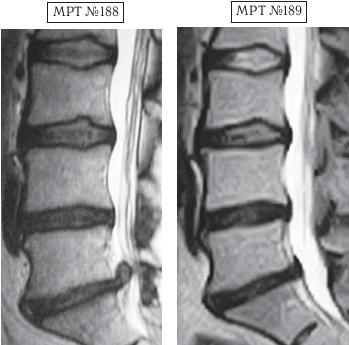

Когда я увидел состояние позвоночника девушки-спортсменки, мне стало жаль её, поскольку было понятно, что пришлось пережить этому стойкому духом человеку. Несмотря на свои молодые годы, как оказалось она уже перенесла операцию по поводу секвестрированной грыжи межпозвонкового диска в сегменте LV-SI. После операции, естественно, были такие же самые нагрузки, которые привели к рецидиву, с чем, собственно, ко мне и пожаловали.

Естественно, грыжи Шморля после лечения никуда не делись, да и дегенеративный процесс в межпозвонковых дисках ещё довольно выражен. Но рецидив — секвестрированную грыжу межпозвонкового диска удалось убрать без повторной операции и при этом практически не снижая нагрузок на тренировках. Но, пожалуй, самое важное, что после лечения методом вертеброревитологии личные спортивные показатели данной спортсменки значительно возросли, причём без всякой химии выросли настолько, что теперь ей приходится улучшать разве только собственные результаты.

На МРТ № 188 наблюдается состояние поясничного отдела позвоночника после хирургического вмешательства: рецидив грыжи межпозвонкового диска в сегменте LV-SI краниальной миграцией секвестра, грыжи Шморля в сегментах LII—LIII и LIII—LIV стеноз спинномозгового канала.

На МРТ № 189 наблюдается состояние после лечения методом вертеброревитологии.